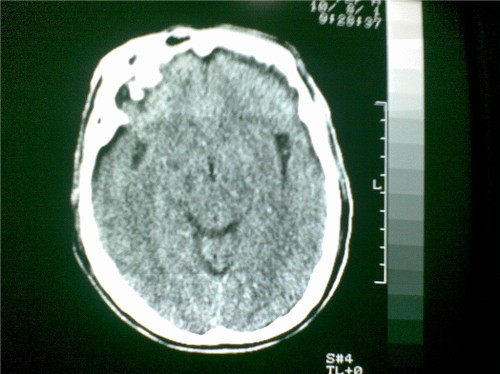

标题: CT28096:男,75岁,外伤10天后,现在恶心、呕吐。是硬膜下积 [打印本页]

标题: CT28096:男,75岁,外伤10天后,现在恶心、呕吐。是硬膜下积

硬膜下积液、右侧基底节、左侧放射冠腔梗。

硬膜下积液、多发性腔梗。

1)双侧额颞顶部硬膜下积液;建议必要时复查。2)多发性腔隙性脑梗塞。